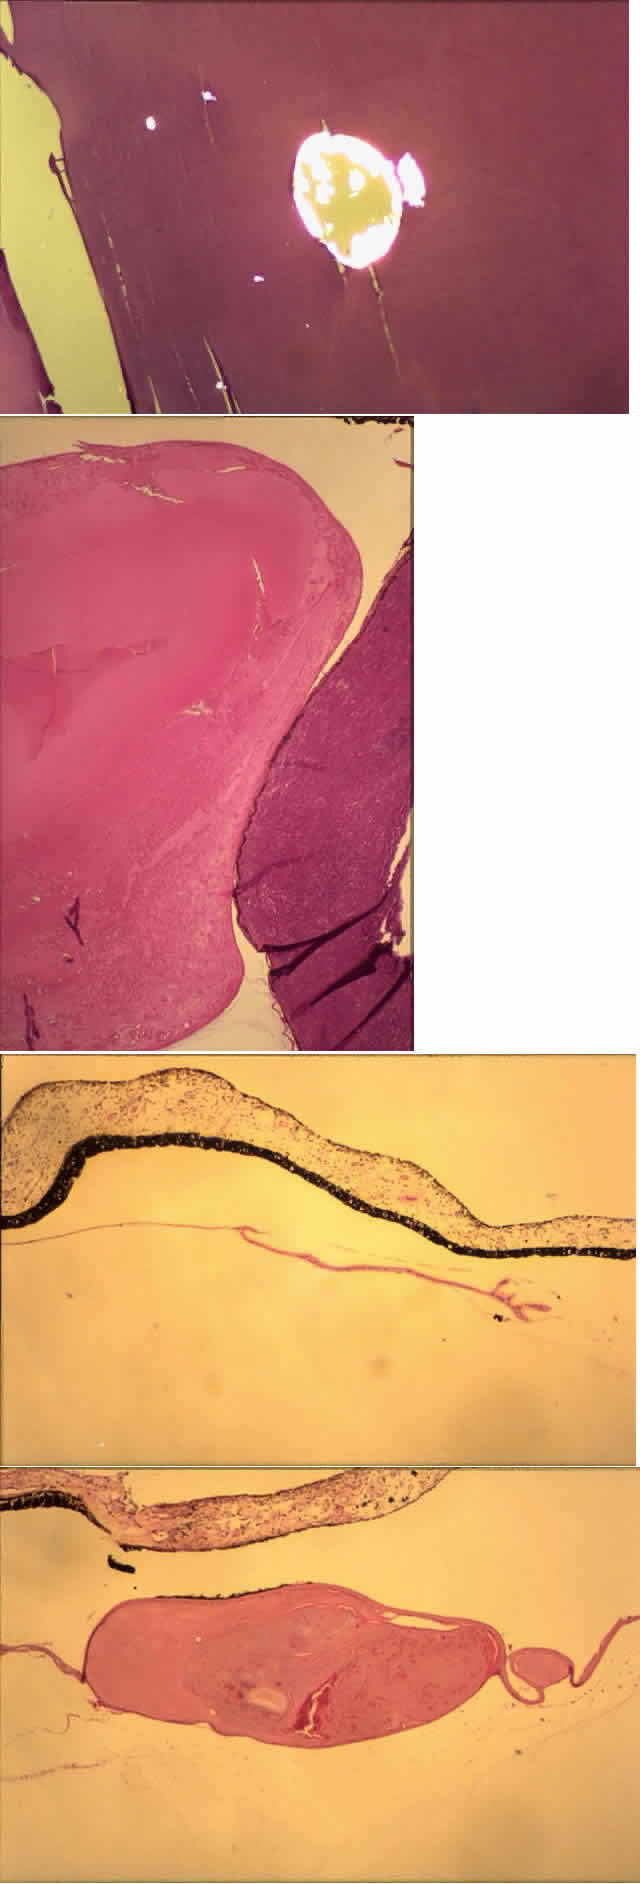

With age, the cortical lens fibers disintegrate and liquefy. The lens proteins are able to leak across a clinically and histologically intact lens capsule. As the proteins escape, macrophages ingest them. As the macrophages accumulate, however, they clog the trabecular meshwork, interfering with aqueous outflow. This is called phacolytic glaucoma (Figs. 10 and 11).62 In the clinical setting, specular microscopy shows these macrophages to be adherent to the posterior corneal surface.63

Fig. 11. Phacolytic glaucoma. A. Hypermature cataract. Most of the cortex leaked through the intact capsule. (N, nuclear cataract). Lens-filled macrophages are shown in high magnification (inset) (arrow). B. Another case shows lens-filled macrophages in the anterior chamber, on the iris surface, in the iris stroma, and in the anterior chamber angle (note angle recession). (A, main figure, PAS, × 70, SEI 73-65; inset, H & E × 220, SEI 73-3; B, H & E, × 220).